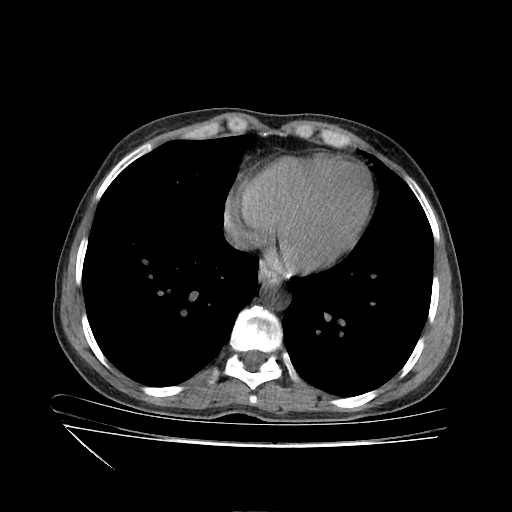

Generated VENOUS CT scan (A→B translation)

Full window (WL 1023.5, WW 4095 β†’ Low βˆ’1024, High +3071)

Lung window (WL -600, WW 1500 β†’ Low βˆ’1350, High +150)

Mediastinum window (WL 40, WW 400 β†’ Low βˆ’160, High +240)